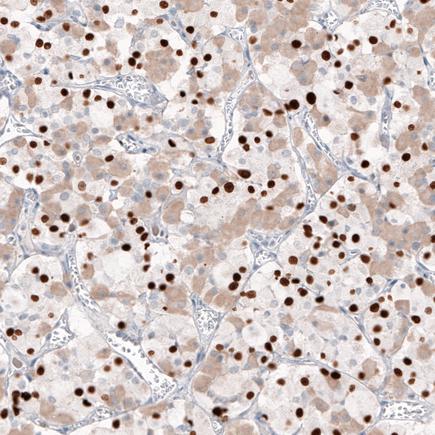

Formalin-fixed, paraffin-embedded human pituitary gland tissue stained for Tpit at a 1:1000 dilution in immunohistochemical analysis.